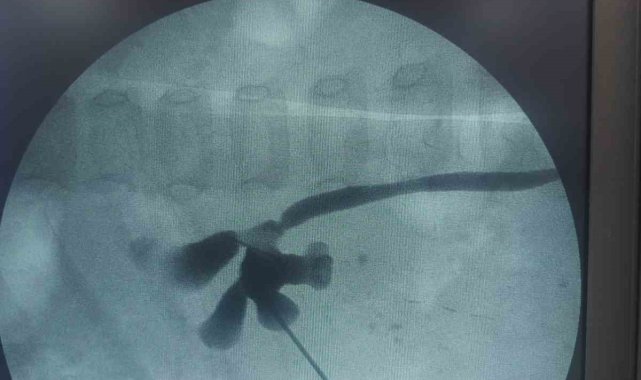

Hastanın yaşı nedeniyle oldukça özel bir operasyon gerçekleştirildiğini belirten Üroloji Kliniği eğitim sorumlusu Doç. Dr. Kadir Yıldırım, "24 aylık bebeğimiz Zeynep'in kapalı böbrek taşı ameliyatını başarıyla gerçekleştirdik. Yavrumuzun böbreğinde 1.5 santimlik bir taş vardı. Süper mini ya da ultra mini PNL diye adlandırdığımız özel aletler kullandık. Bebeğimizin durumu şu an gayet iyi" dedi.

Elazığ Fethi Sekin Şehir Hastanesi, başarılı sağlık hizmetlerine bir yenisini daha ekledi. Türkiye genelinden hastaların başvurduğu hastanenin Üroloji Kliniği, bu kez Bingöl'den gelen iki yaşındaki bir hastayı sağlığına kavuşturdu. Karın ağrısı şikayetiyle hastaneye getirilen 24 aylık Zeynep Neva B.'nin böbreğinde 1.5 santimetrelik taş tespit edildi. Yapılan tetkiklerin ardından, başarılı bir şekilde kapalı böbrek taşı ameliyatı olan küçük Zeynep, tedavi sürecinin sonunda taburcu edildi.